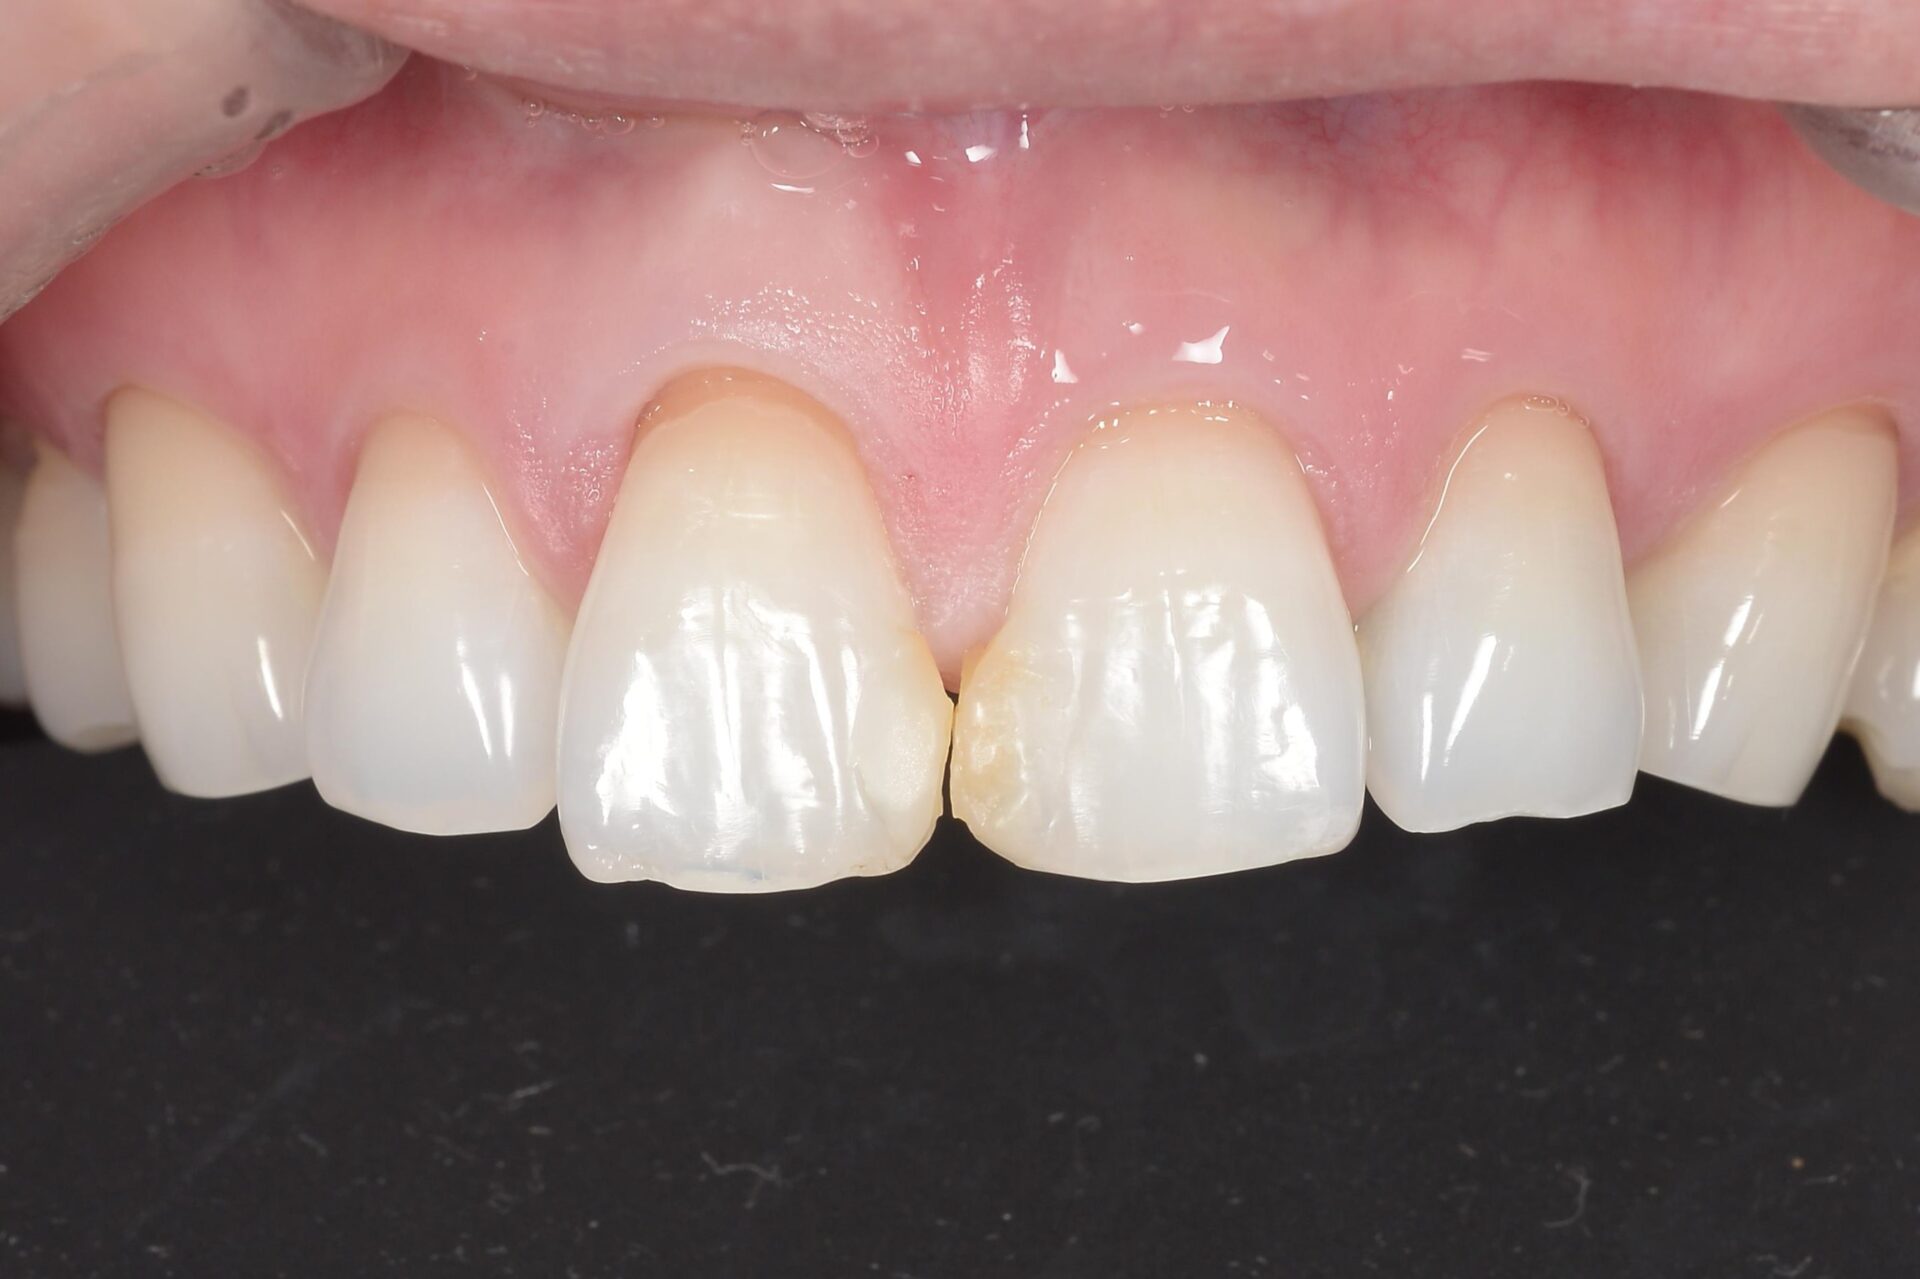

審美治療

前歯の詰め物が気になる。被せ物の色が気になる人へ

Before

After

| 年齢 | 20代 |

|---|---|

| 性別 | 女性 |

| 治療期間 | 約4ヶ月 |

| 治療方法 | 右上2番根管治療および、オールセラミッククラウン、左右1番ラミネートべニア |

| 治療費用 | 右上2番根管治療~オールセラミッククラウン約40万、左右ラミネートべニア約17万×2 |